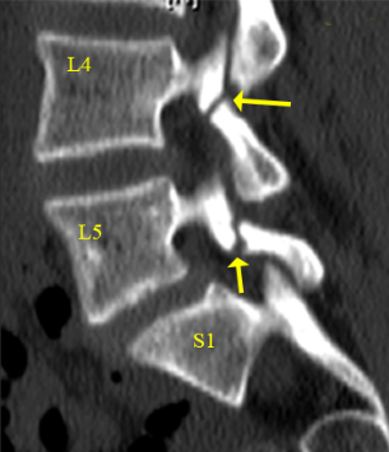

The surgeon removes the damaged disc or diseased bone, places a cage or bone graft between the vertebrae, and secures it with screws and rods. Over months, the bones heal together naturally. The surgical approach (front, back, or side) depends on the patient's specific condition and body type.

- Restoration of stability in the spine

Patients usually stand or walk the next day. Office work can restart in 4-6 weeks, and full bone healing takes 3-6 months. In some cases, a brace may be used for extra support.